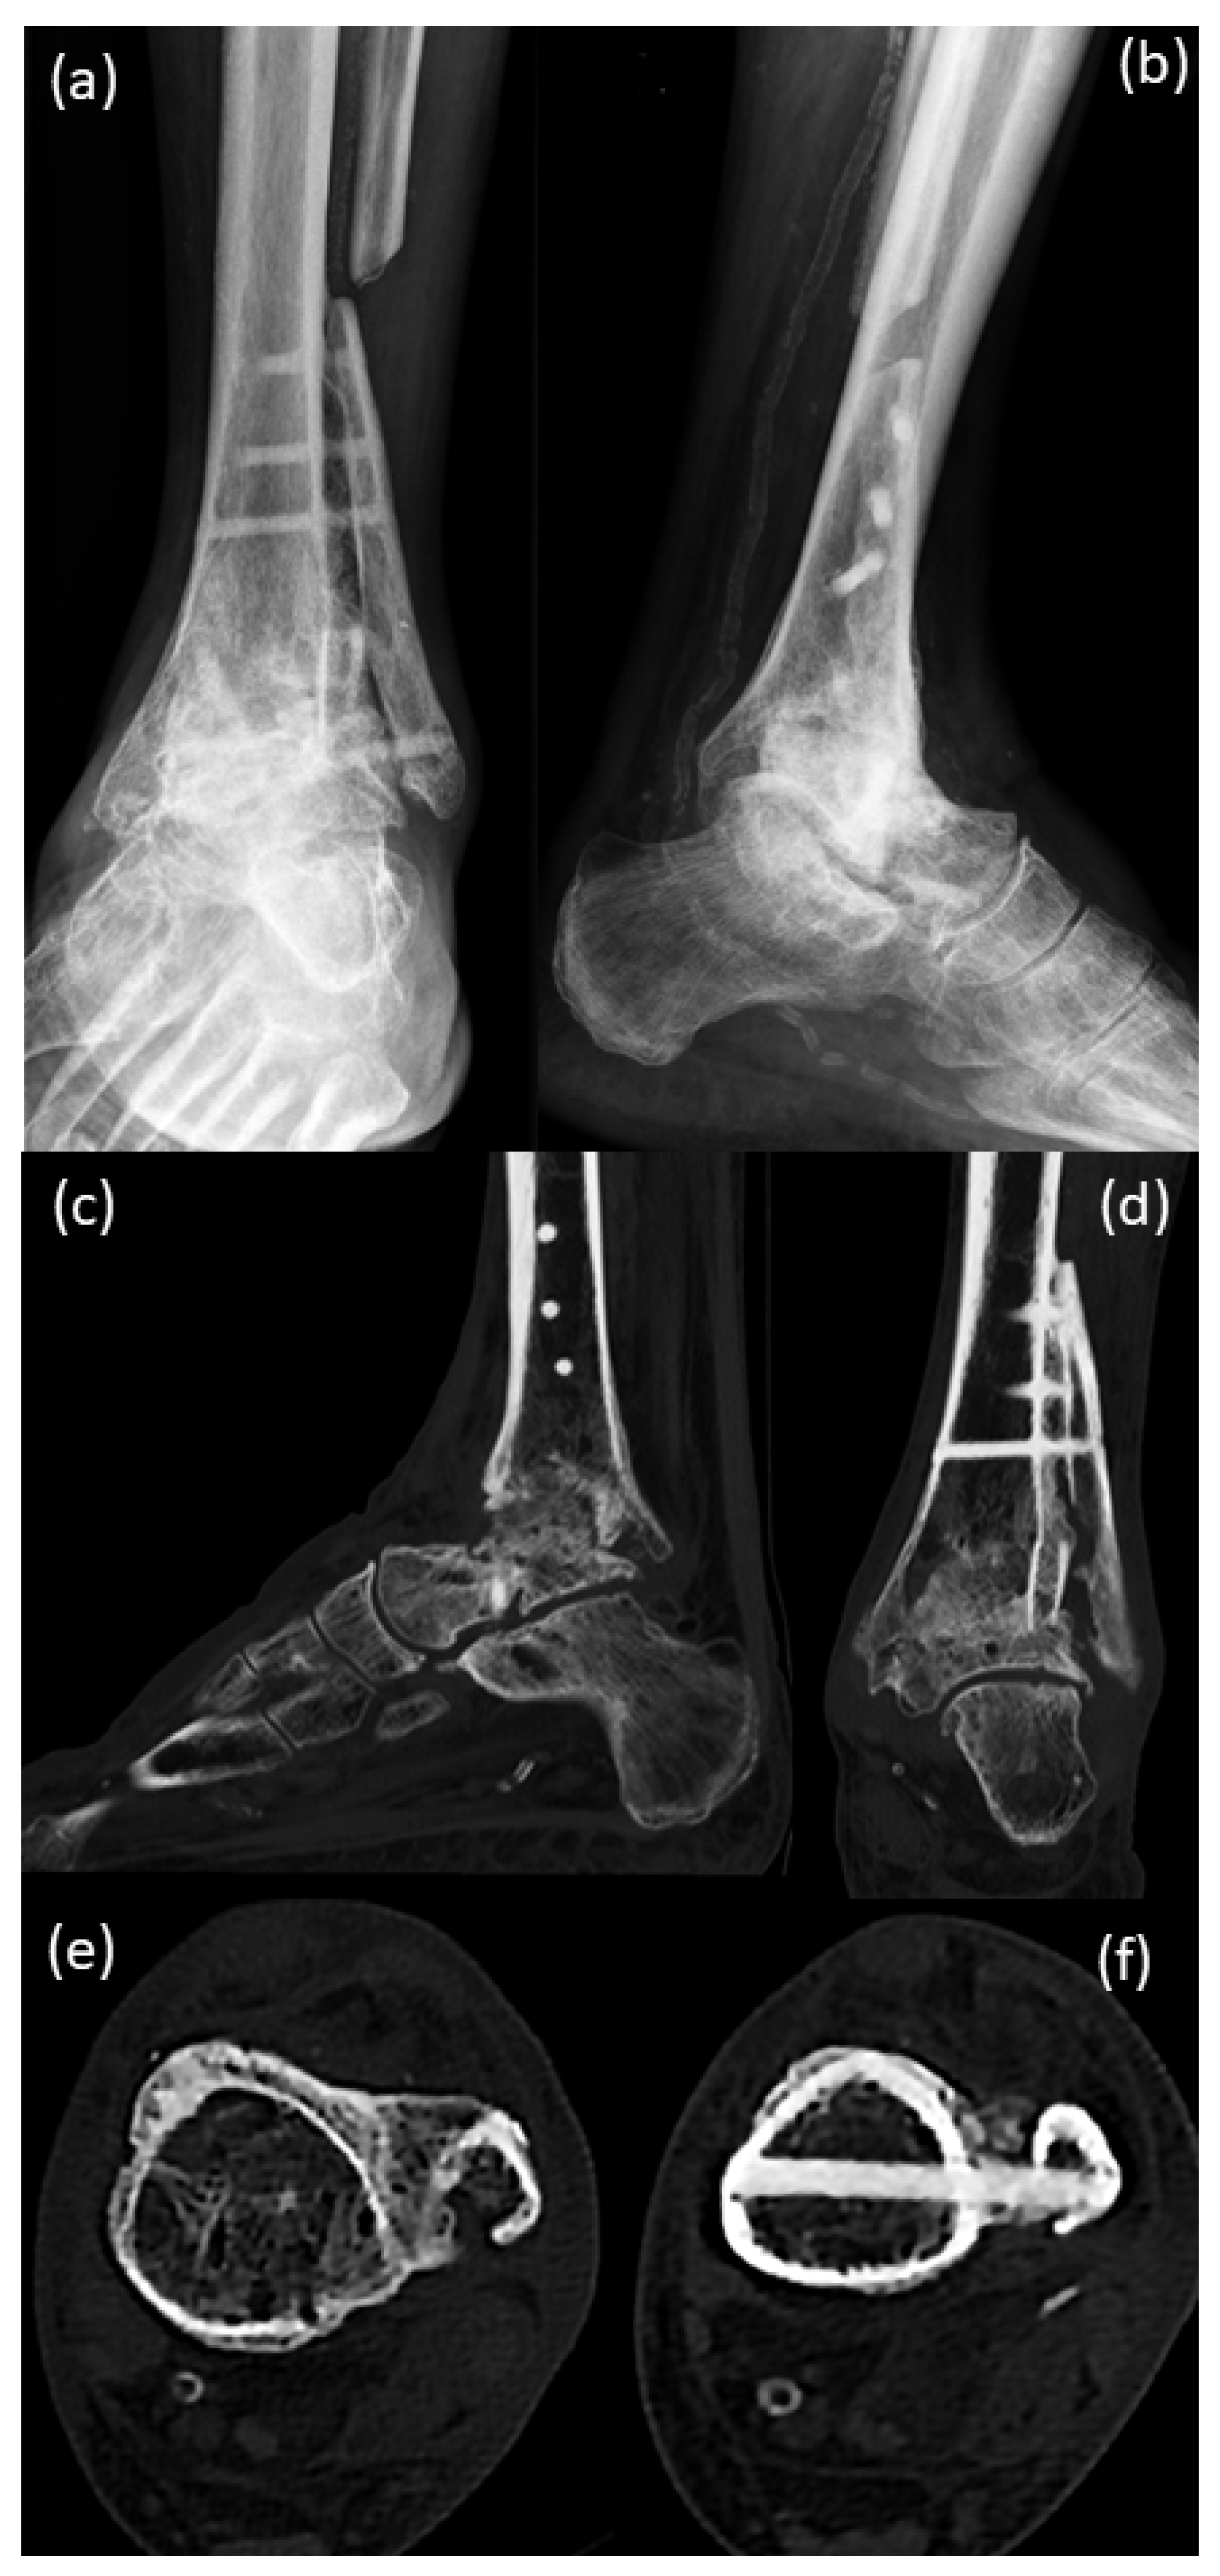

4. Postoperative Rehabilitation

5. Results